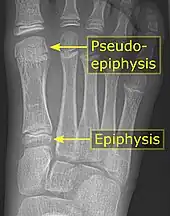

First metatarsal bone. Deep dissection. It is common in children to have a pseudo-epiphysis of the first metatarsal.[5]

It is common in children to have a pseudo-epiphysis of the first metatarsal.[5]